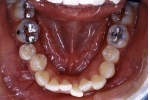

マルチブラケット終了時